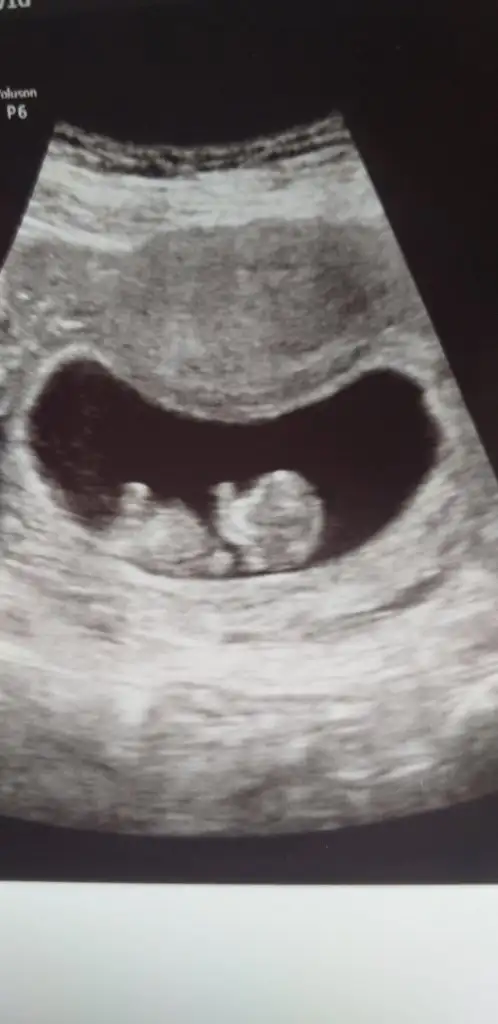

Ikra meyra Ikra meyra canım sen galiba baya bilgilisin bu konuda 😌 bizim hakkımızdaki tahminin nedir? 11+1 idi ama ultrasonda 11+4 çıktı ancak doktor emin olmadıgı için söyleyemedi cinsiyeti :)

Ikra meyra Ikra meyra bir de böyle bir görüntü de var canım